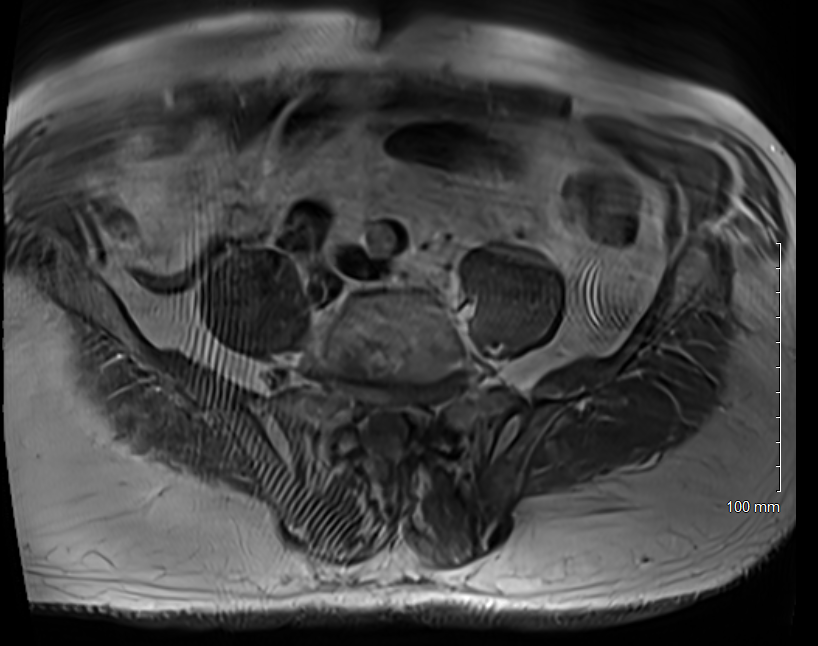

We saw this artifact on several slices of a T1weighted scan (tse2d1_3)

obtained on a 3T Siemens Skyra. I suspect the subject’s arms and hands are

by their side and as the FOV is pretty small, 320 mm, they may be outside

the FOV even with oversampling. Any other thoughts to explain the wavey

lines?

That is an interesting artifact. At first glance, it looks like Moire or

spike. However, it seems quite unlikely to be Moire due to the pulse

sequence being a fast spin echo. GRE or bSSFP are the usual culprits for

Moire. Assuming the phase-encode is L/R (to minimize respiratory motion

ghosting in main region of interest) and parallel imaging is on, I would

agree with you in assuming the likely cause is inadequate oversampling. The

other possibility is that a spike is occurring in a specific coil channel

that is then propagating irregularly in the image due to the parallel

imaging recon. I have seen that happen on a GE system. If the rawdata is